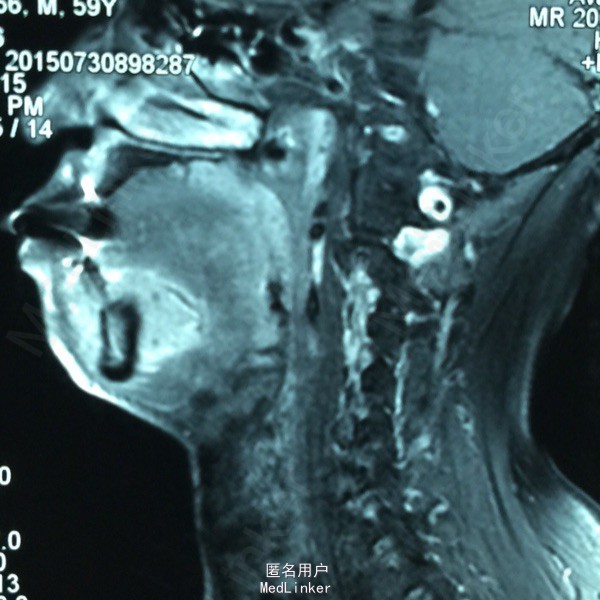

患者男性,59岁,因‘口腔溃疡8月余,进食困难伴疼痛3月余’入我院,8月前,患者自觉口腔溃疡到当地医院就诊,诊为口腔溃疡,给予保守药物治疗,服抗生素无明显好转,3月前出现进食困难伴疼痛,舌体运动障碍,未予重视,2月前就诊我院,给予活检证实口底鳞癌。

查体见口底C5-D5区域查见约5*4厘米外生菜花状肿块,累及唇黏膜,唇舌侧牙龈,口底,舌腹,与下颌骨界限不清,骨膜受侵,舌体动度差,c3,4 d3,4二度松动,右颈1-2区多发肿大淋巴结,最大直径约2厘米。 CT提示下颌体中央区骨质及部分牙槽突破坏,软组织增厚占位,与口底增厚强化软组织分界不清。双颈多发肿大淋巴结

诊断口底癌伴颈淋巴结转移 T4N2M0. 处理 给予2周期TP方案化疗。方案为 顺铂 30mg d1-3,紫杉醇 210mg d1*21d*2周期,化疗结束后给予根治性双颈淋巴清扫术,口底病灶扩大切除术,下颌骨c5-d5箱状切除术加右胸大肌皮瓣修复术